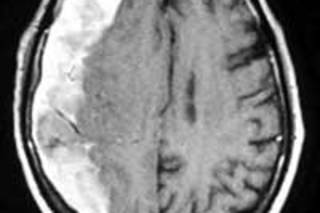

As the years go by, the adult brain slowly atrophies, like a desiccated orange detaching from its rind. The shrinkage can cause problems. Cerebral veins are tethered to the superior sagittal sinus, the large blood vessel that runs front to back along the underside of the skull. As the brain contracts, these bridging veins must stretch, making them vulnerable to shearing forces caused by rapid head movements or even modest contusions. Without sufficient brain tissue to support and compress the bleeding site, small, low-pressure venous leaks may go unstanched. The blood seeps into the gap between the arachnoid membrane that encloses the brain and the lining of the skull, or dura mater. Bleeding into this space is called a subdural hematoma.

Acute subdural hematomas result from severe head trauma and expand quickly. Chronic subdural hematomas, on the other hand, often spread slowly—and without visible symptoms. What really scares emergency physicians—and has me repeating to patients and their families, "Return if there's any change in behavior"—is that older people who have fallen can look fine for weeks before the bleeding causes symptoms. By then, relatives will have forgotten the long-ago head knock, attributing Granddad's confusion to the heat, the cold, or a dizzy spell. Without that critical, sometimes lifesaving clue, precious time is lost.

Forty-five minutes later, the radiologist called. "Your patient has a big subdural on the right. Evidence of old bleeding too. How is he doing?"

In the operating room, the neurosurgeon drilled four small holes in the skull, sawed between them, and lifted off a rectangle of bone the size of a credit card. The dura mater beneath was tense and black, bulging with clotted blood. The surgeon incised twice to make an X, allowed the accumulated blood to pour out, then carefully irrigated the surface of the brain while looking for signs of persistent bleeding. When everything looked good, he placed a flat rubber drain inside the incision, replaced the bone flap, stitched the scalp closed, and stapled the skin shut. Done.